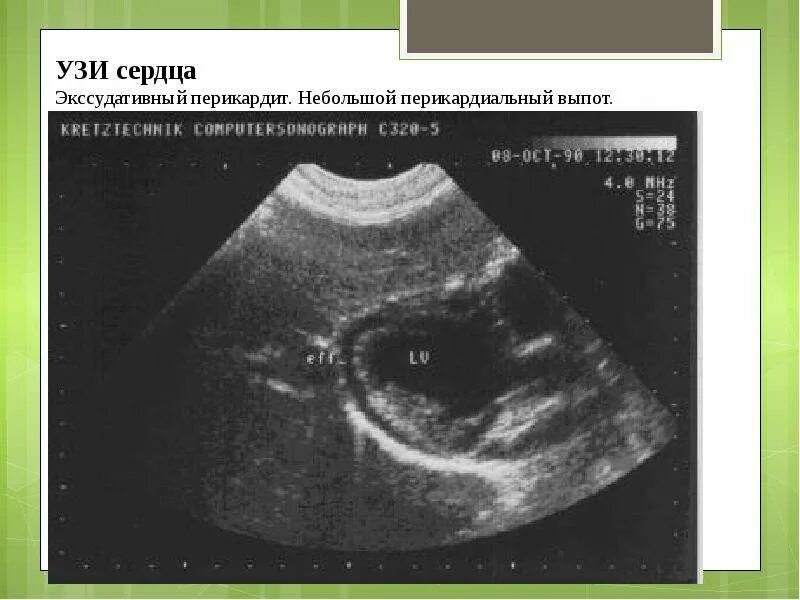

Выпотной перикардит эхокг. экссудативный перикардит эхокардиография. жидкость в перикарде сердца эхокг. жидкость в полости перикарда на эхокг.

Жидкость в полости перикарда. норма жидкости в перикарде по узи. наличие жидкости в полости перикарда.

Экссудативный перикардит эхокг. экссудативный перикардит эхокардиография. экссудативный перикардит узи. фибринозный перикардит эхокг.